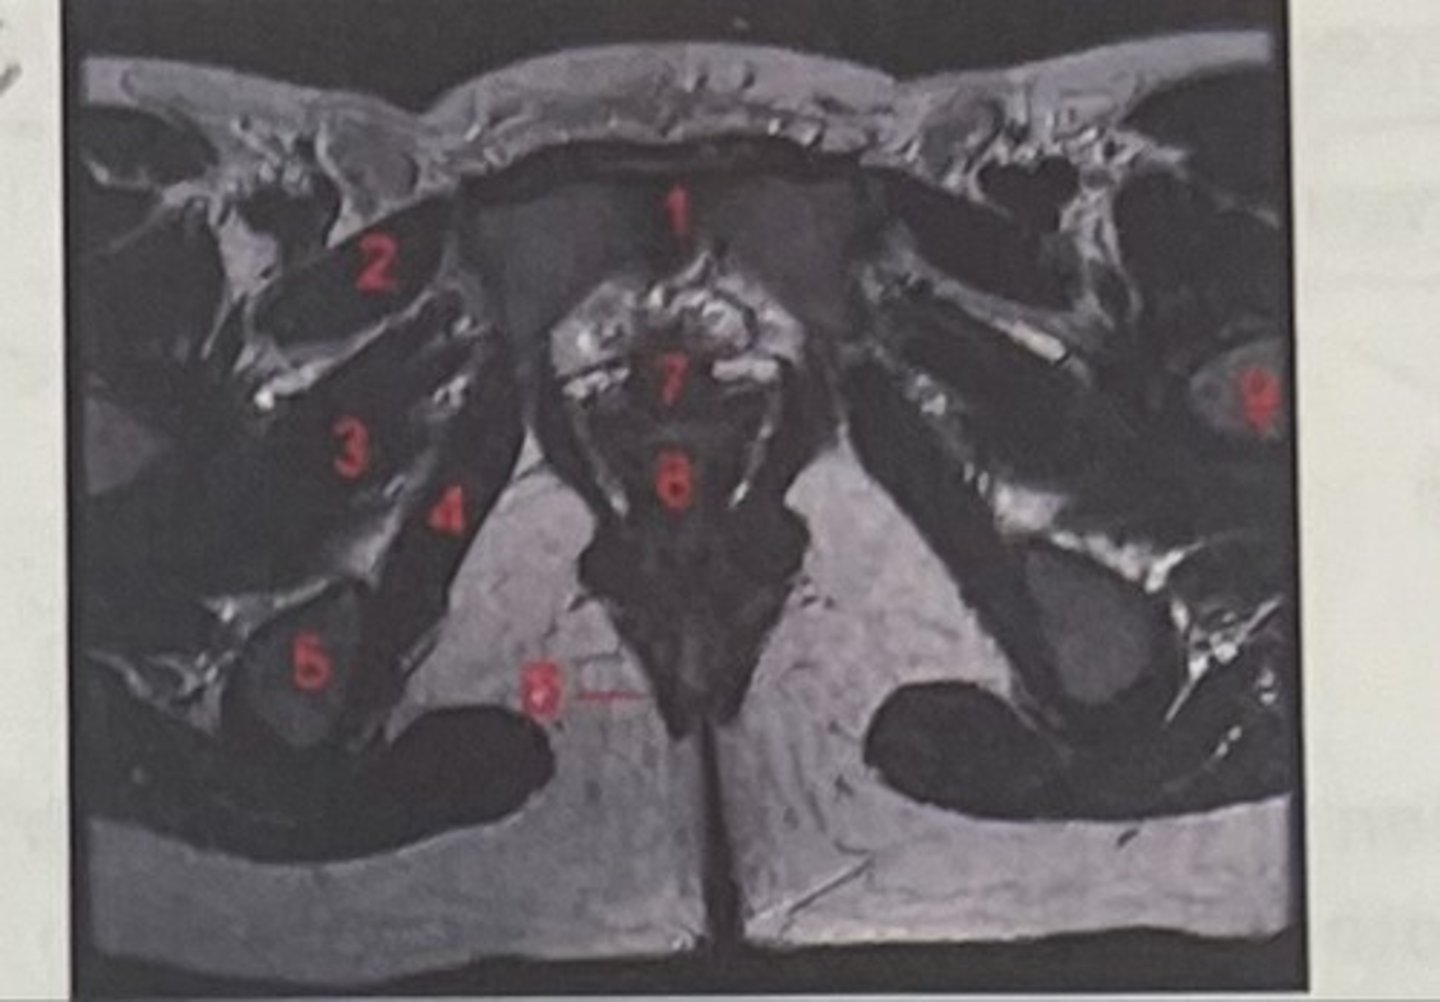

pubic symphysis

What is 1

Pectineus

What is 2

Obturator externus

What is 3

obturator internus

What is 4

ischial tuberosity

What is 5

external spincter

What is 6

Urethra

What is 7

Vagina

What is 8

Femoral nerve

What is 9

Left lung